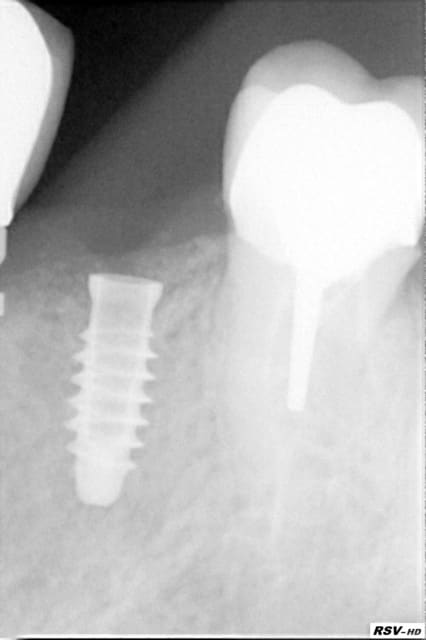

Patient ayant eu une EIMCI avec pilier Peek en ....2011!

Ces piliers ne sont pas fait pour encaisser les forces de mastication. La sentence est tombé: Fracture dans l'implant du piler 4 ans après. (3 premières photos)

Après des tentatives infructueuses de retirer la partie "soudée" dans l'implant la décision fut prise de remplacer cet implant. Il est parfaitement ostéointégré et dans ce cas ceux qui en ont posé savent qu'il impossible de le dévisser sans fracture osseuse même lors de son placement.